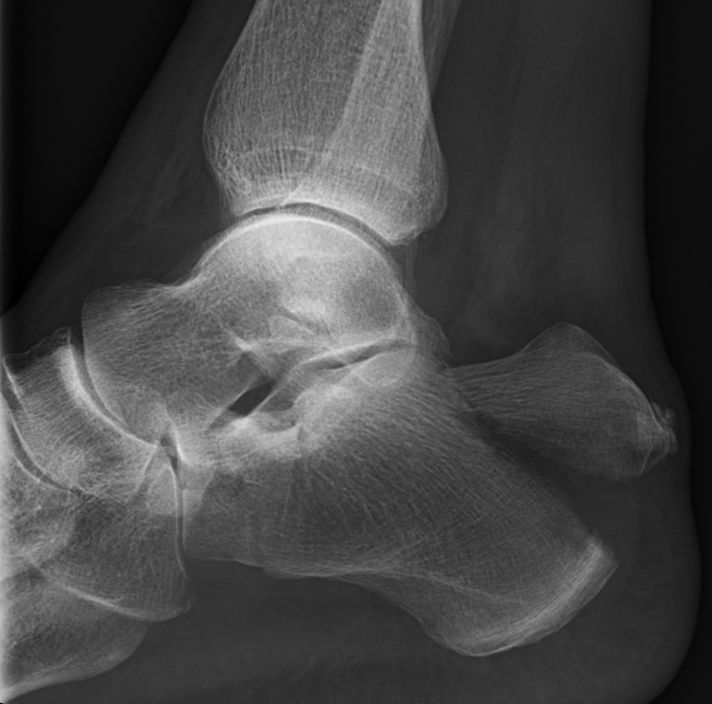

Tungfraktur = beakfraktur: kalkaneus har delat sig så fästet för akillessenan dras proximalt. Ger stor risk för snabb nekrosutveckling pga tryck mot huden.

Tungfraktur

- Tungfraktur ska opereras med 2-3 grova kanylerade skruvar så snabbt som möjligt, helst även nattetid